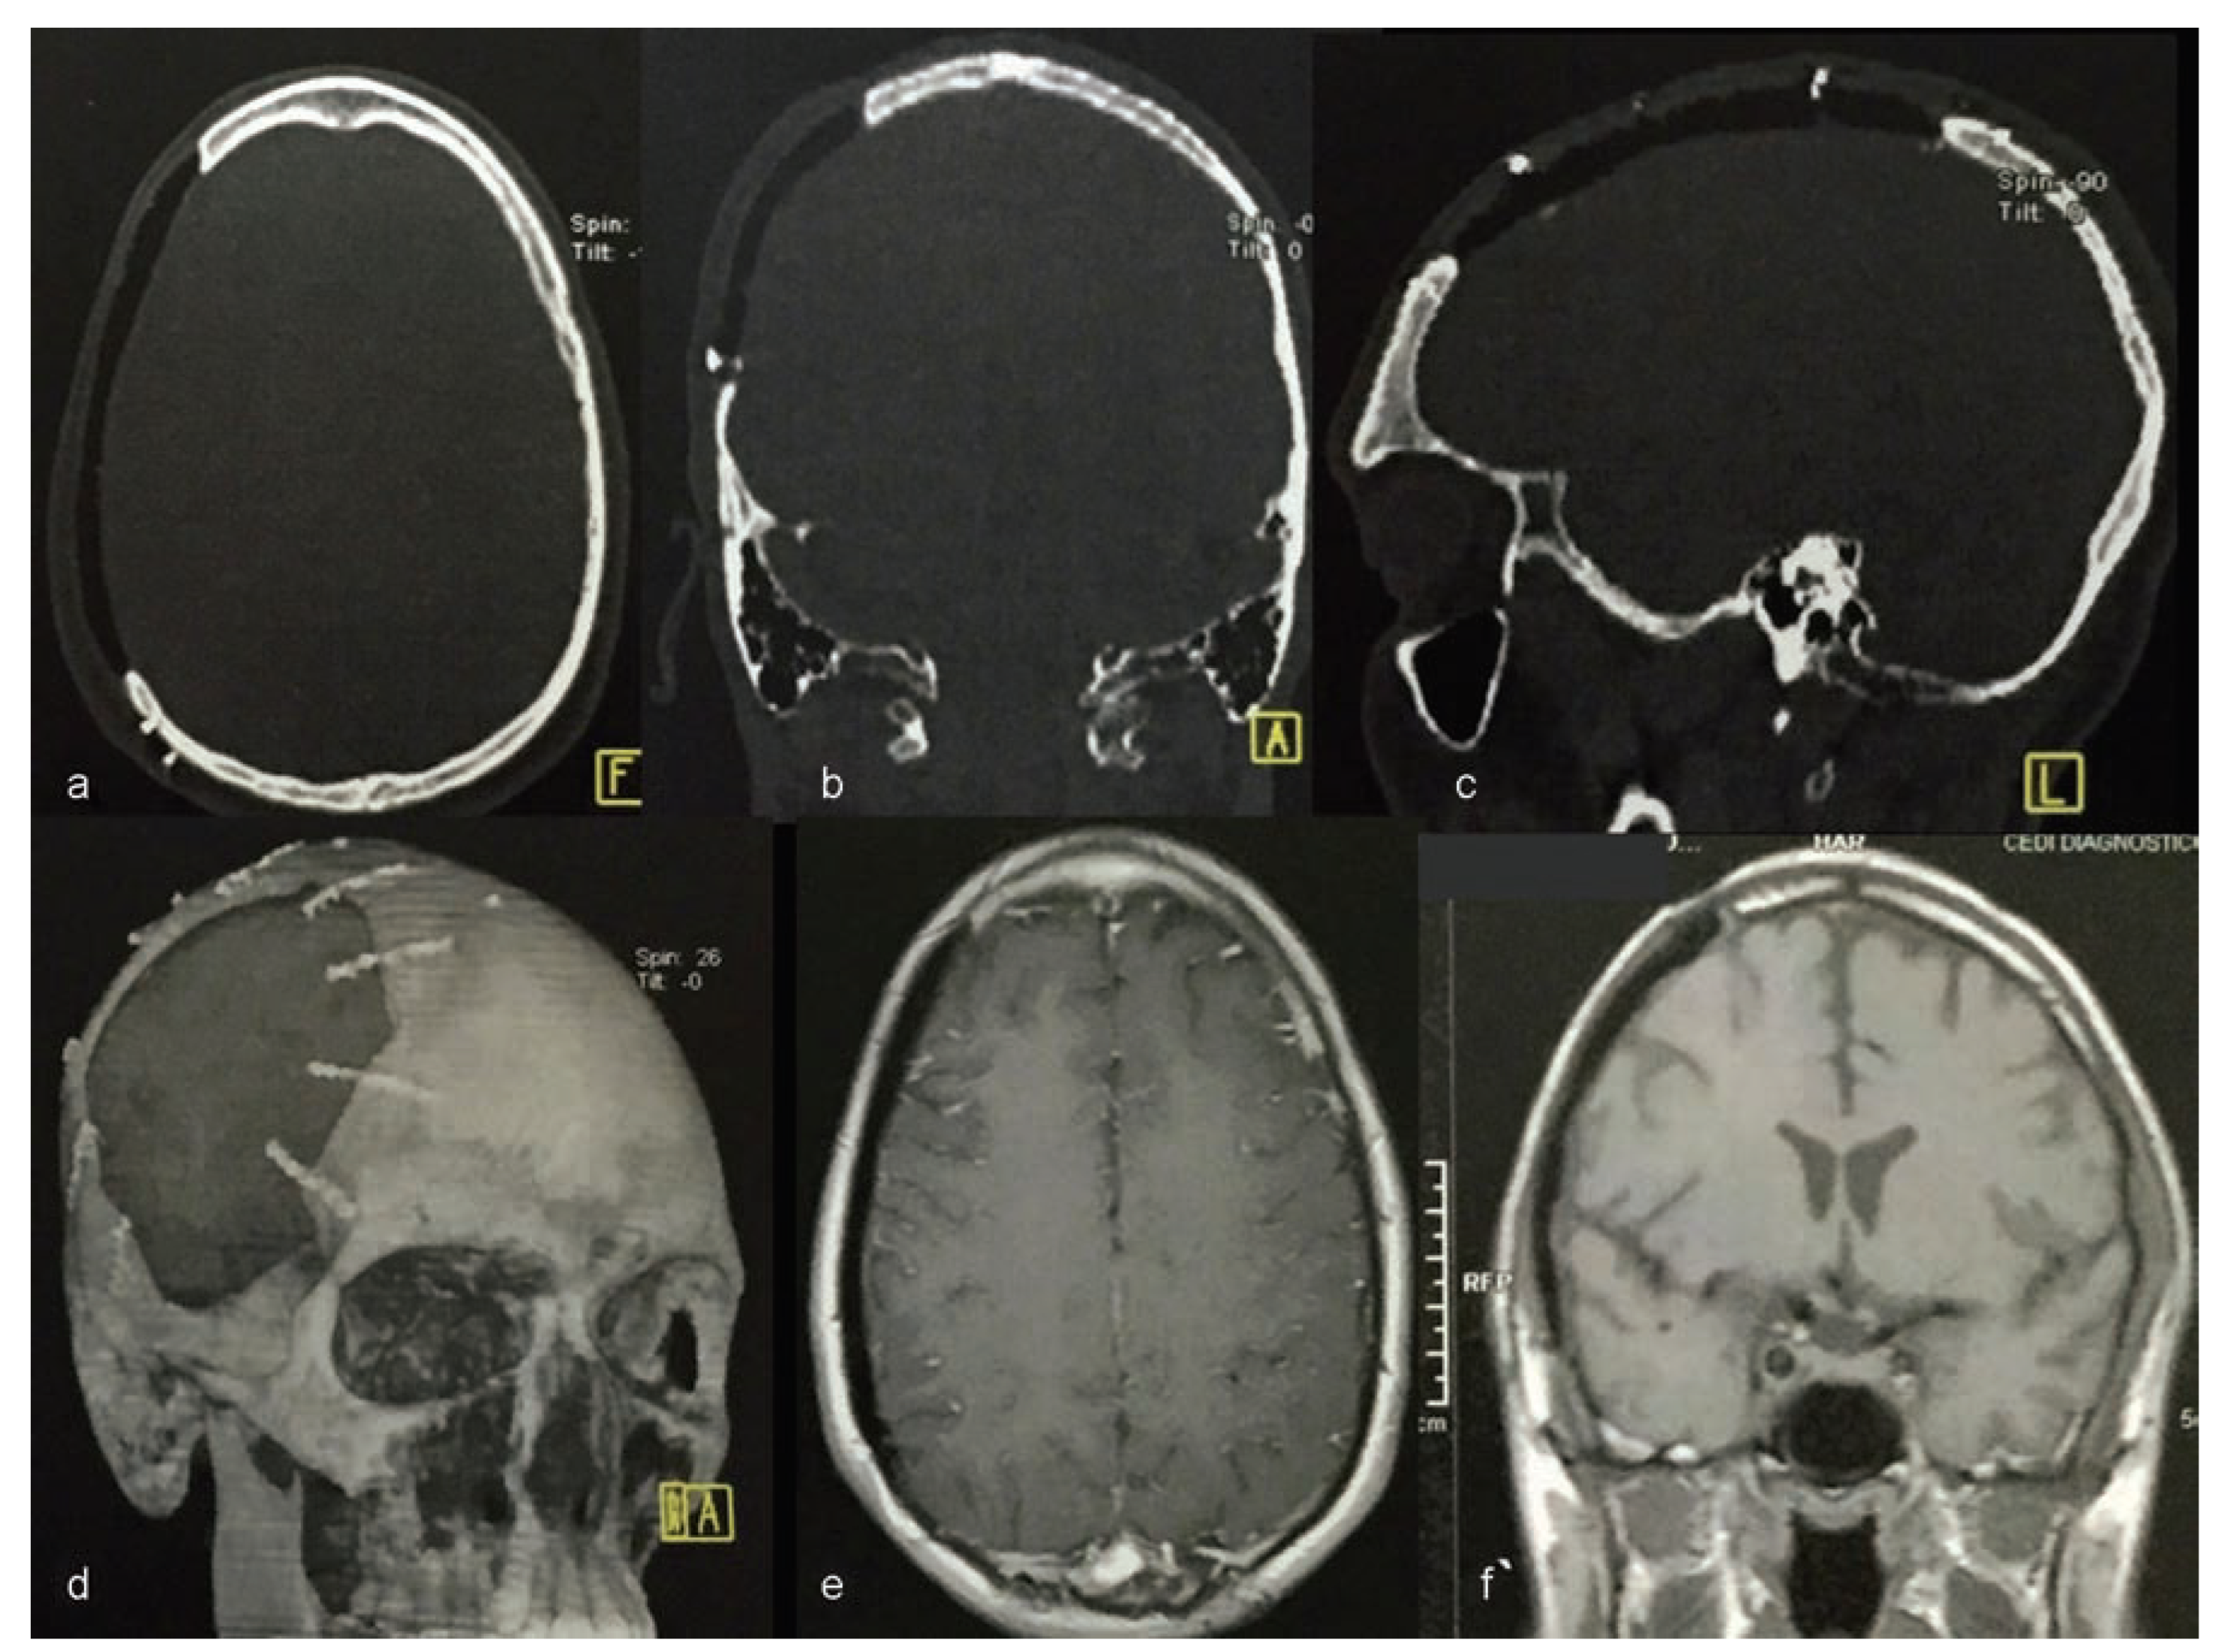

Computerized tomography (CT) was conducted using a 4-channel helical CT scanner Medical Toshiba Asteion 4-slice CT Scanner (Toshiba America Medical Systems, Inc., Tustin, CA). Axial, coronal, and sagittal sections and three-dimensional (3D) reconstruction were conducted (Figure 3).

The CT scan enabled the construction of the prototype prosthesis using the castor bean polymer. This was done to protect the brain and to rebuild the general anatomical contours of the skull.

Figure 3. (a,b) Computed tomography with three-dimensional reconstruction.